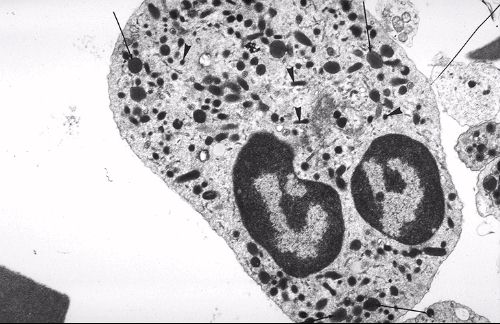

microscopie électronique à transmission MET (technique de BASE + techniques spéciales qui englobent cryomicroscopie, marquage à l'or et ombrage) a une résolution (maximale) de

0,2 nm => Rappelez vous qu'on peut visualiser des organites +++

Polynucléaire neutrophile (cellule sanguine)